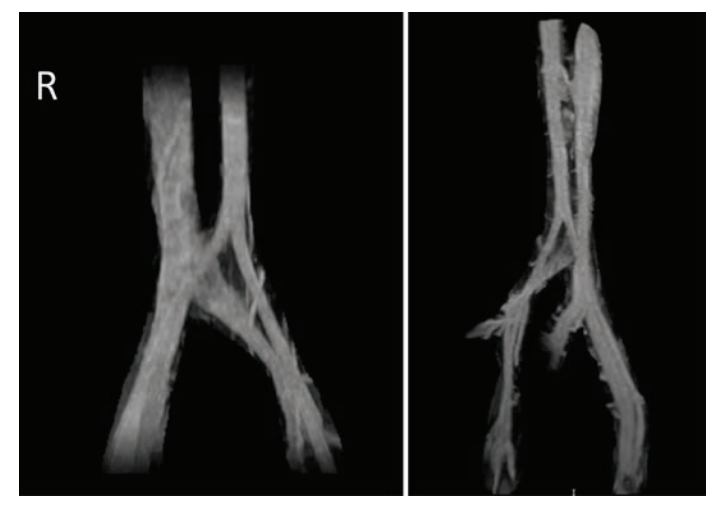

A 39-year-old woman with a history of recurrent deep vein thrombosis (DVT), pulmonary embolism (PE), and protein C deficiency on oral anticoagulation (OAC) was referred to our clinic for chronic bilateral lower extremity swelling, redness, and varicose veins. She was initially diagnosed with DVT and PE in 2003, for which she was on OAC with warfarin. Her warfarin was discontinued 6 months later, and she did well until 2018 when she had a recurrent DVT and PE following an 8-hour plane ride. At that time, a workup revealed a protein C deficiency, and she had been on OAC with apixaban 5 mg twice daily ever since. Her leg swelling, redness, and pain became severe a few weeks before presentation, which was aggravated by standing for long periods. She also complained of frequent dyspareunia and periodic pelvic pain. On physical examination, she was noted to have varicose veins on both legs, 2+ pedal edema up to the level of the thigh, and redness in both legs. We ordered a venous ultrasound (US) of the lower extremity to assess for reflux and to rule out DVT. We ordered a magnetic resonance angiography (MRA) with the suspicion of a central venous obstruction and PCS. Her US showed a chronic, nonocclusive thrombus in the left common femoral vein (CFV). Her MRA showed effacement of the proximal left iliac vein by the right common iliac artery, which was consistent with May-Thurner syndrome (Figure 1). In addition, the MRA showed varices of the anterior pelvic wall. We performed venography with intravascular US (IVUS)-guided percutaneous transluminal angioplasty (PTA) and stent placement. US-guided access was obtained from both right and left popliteal veins, and 8 Fr sheaths were inserted. Contrast venography was performed to both the deep femoral and iliac veins, demonstrating vessel patency throughout with visually apparent luminal narrowing in the left iliac vein. IVUS confirmed a 40% compression of the right external iliac vein (EIV) and a diffuse 80% fibrotic stenosis of the left common iliac vein (CIV) to CFV (Figure 2A). Extensive pelvic collaterals were also noted (Figure 2B). We performed PTA of the left CIV with a 16 mm x 40 mm Atlas Gold balloon (BD). Following balloon angioplasty, through the 8 Fr sheath, we deployed a 16 x 140 mm Zilver Vena stent from the left CIV into the EIV and deployed another 16 x 60 mm Zilver Vena stent overlapping with the first stent from the EIV into the CFV. The stents were post-dilated with the same Atlas Gold balloon, and a postprocedure venogram and IVUS showed excellent results, with complete resolution of the pelvic collaterals (Figure 2C). She was discharged home on clopidogrel 75 mg daily in addition to the apixaban 5 mg twice daily that she was already on. On a follow-up visit 1 month later, the patient reported significant reduction of her lower extremity edema, pain, and redness. On a 6-month follow-up, she reported complete resolution of these symptoms as well as pelvic pain and dyspareunia.